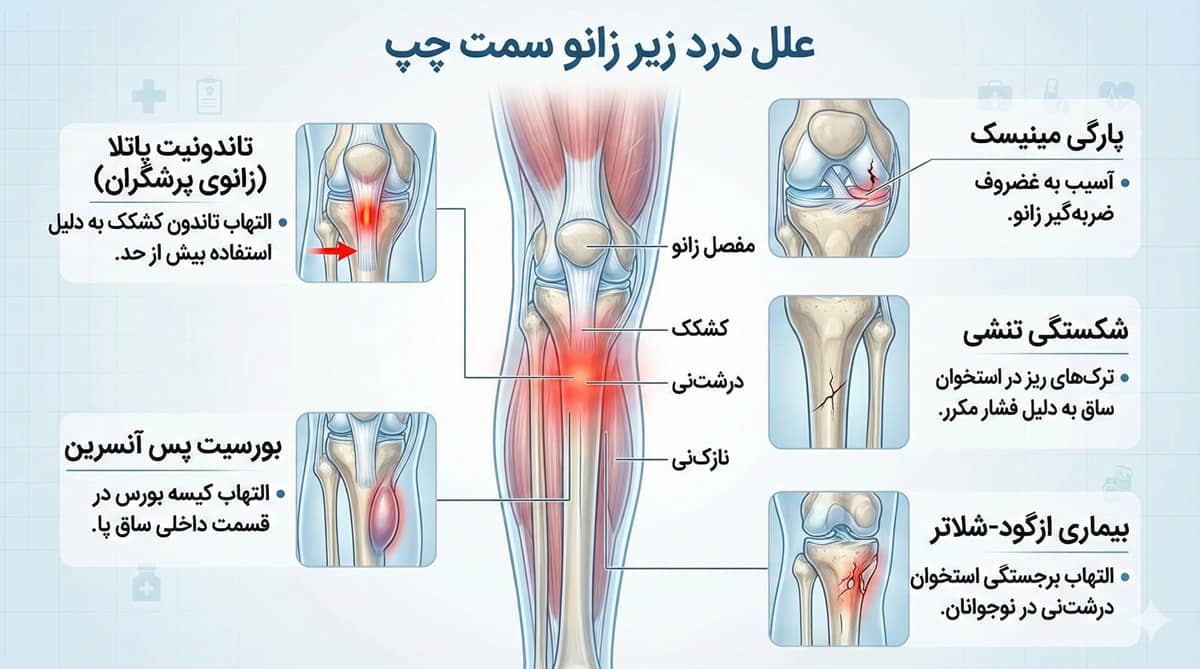

«به عنوان مثال، درد زیر کشکک زانو میتواند نشانهای از تاندونیت پاتلار یا همان التهاب تاندونی باشد که کشکک زانو را به استخوان درشتنی متصل میکند.»

برای درک بهتر درد زیر زانو، ابتدا باید با ساختار این مفصل آشنا شویم. زانو از چندین بخش تشکیل شده است: استخوان ران (فمور) که از بالا، استخوان درشتنی (تیبیا) که از پایین، و استخوان کشکک (پاتلا) که در جلوی زانو قرار دارد. علاوه بر این، رباطها، تاندونها، منیسکها (غضروفهای هلالی) و کیسههای مایع سینوویال نقش مهمی در حرکت و ثبات زانو دارند. هر یک از این ساختارها میتواند منشأ درد باشد. موقعیت دقیق درد (زیر زانو، پشت زانو، داخل یا خارج زانو) به پزشک کمک میکند تا علت اصلی را شناسایی کند.

-تاندونیت کشکک (زانوی پرشی):

تاندونیت کشکک یکی از شایعترین علل درد زیر زانو است. این عارضه زمانی رخ میدهد که تاندون پاتلار (که کشکک را به درشتنی متصل میکند) در اثر فشار مکرر ملتهب شود. ورزشکارانی که پرش زیادی دارند مانند بسکتبالیستها و والیبالیستها بیشتر در معرض این آسیب هستند. علائم شامل درد در ناحیه زیر کشکک، حساسیت به لمس و تشدید درد هنگام پرش یا پله رفتن است.

-بیماری ازگود اشلاتر:

این بیماری یکی از علل اصلی درد زیر زانو در نوجوانان است و معمولاً در سنین ۱۰ تا ۱۵ سالگی رخ میدهد. در دوران رشد سریع، تاندون کشکک به برجستگی استخوان درشتنی (توبروزیته تیبیا) فشار وارد میکند و باعث التهاب و برجستگی دردناک زیر زانو میشود. این درد معمولاً با فعالیت بدنی تشدید و با استراحت بهتر میشود. خوشبختانه این بیماری با پایان دوران رشد به طور خودبهخود بهبود مییابد.

-بورسیت زانو:

بورسیت التهاب کیسههای کوچک پر از مایع (بورسا) است که به کاهش اصطکاک بین بافتها کمک میکنند. بورسیت در ناحیه زیر کشکک میتواند باعث درد زیر زانو همراه با تورم و گرمی شود. این عارضه در افرادی که زیاد زانو میزنند (مانند کاشیکارها یا باغبانها) شایعتر است.

-سندرم درد پاتلوفمورال (زانوی دونده):

این سندرم به درد در اطراف و زیر کشکک اشاره دارد و در دوندگان بسیار شایع است. علت دقیق مشخص نیست، اما عدم تعادل عضلانی، ضعف عضلات ران و مشکلات آناتومیک مانند کف پای صاف میتوانند در بروز آن نقش داشته باشند. درد معمولاً هنگام بالا یا پایین رفتن از پلهها، نشستن طولانیمدت یا چمباتمه زدن تشدید میشود. این مشکل در خانمها بیشتر دیده میشود.